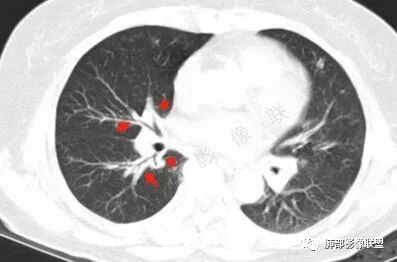

胸CT:双中下肺支气管壁明显增厚,双下肺胸膜下可见实变区。部分病变呈楔形影。

双肺多发大小不等结节,周围伴有晕征,边界模糊,部分结节内似可见支气管影,双肺血管束明显比支气管增粗,临床有感染症状,考虑GPA,疱疹病毒。

双肺支气管管壁弥漫性增厚,管腔狭窄,下叶为主,伴多发高密度结节影,边缘模糊,双肺支气管血管束明显增粗,临床症状咳嗽低热,有血尿,首先考虑血管炎

影像上:多发结节沿血管分布;双下叶支气管血管束简直增厚,偏血管,支气管通畅

因为支气管壁增厚,远端应该小气道病变,这个不是,反而是血管增粗明显

加上结节的分布,支持血管相关病变

两肺多发结片影,这个病灶很小,但是中间可见支气管影,支气管炎一般不会包在支气管周围,支气管周围间质可能大,包括血管,淋巴等。一般支气管这样穿行的,被包绕的,血管炎,淋巴瘤等这种间质起源比较多见